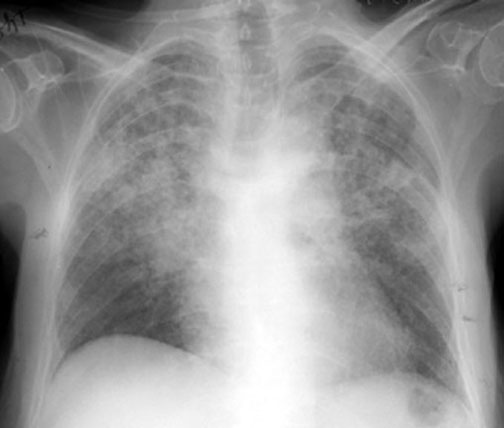

Hamman-Rich Syndrome

Rapid progression of interstitial disease